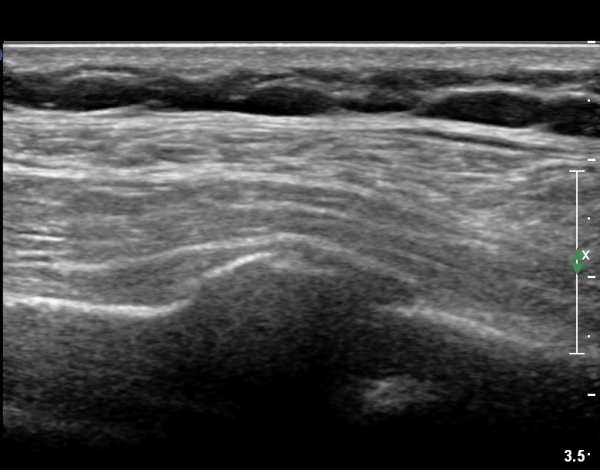

on moving of prove a little, there is bony protrusion(osteoblastic lesion) and hypoechoic(osteolytic)  lesion(image 2, 3, 4).

in transverse scan, visualization of osteoblastic mass with central osteolytic lesion(image 5, 6).

As like this case, visualization of osteoblastic lesion and osteolytic lesion in simultaneously  suggests a malignant mass.